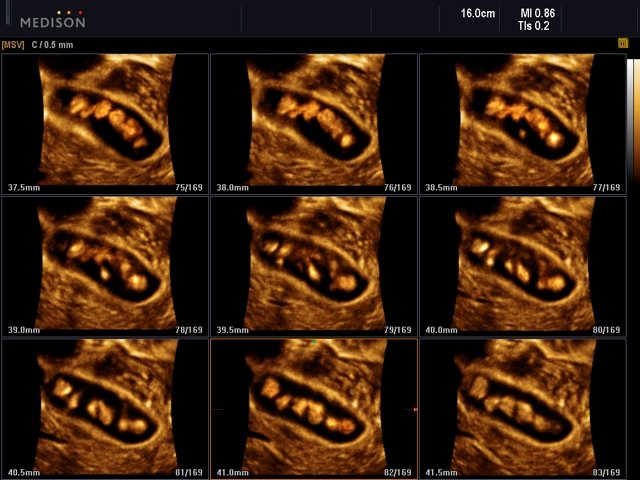

Multiple gallbladder stones, MSV+HDVI & 3D

Multiple gallbladder stones, MSV+HDVI & 3D (echogramm №538)

[RU] Ultrasound image №538: Multiple gallbladder stones in multi-slice 3D reconstruction mode (HDVI used).

Echogramm was received by ultrasound scanner Accuvix-XG (out of production).